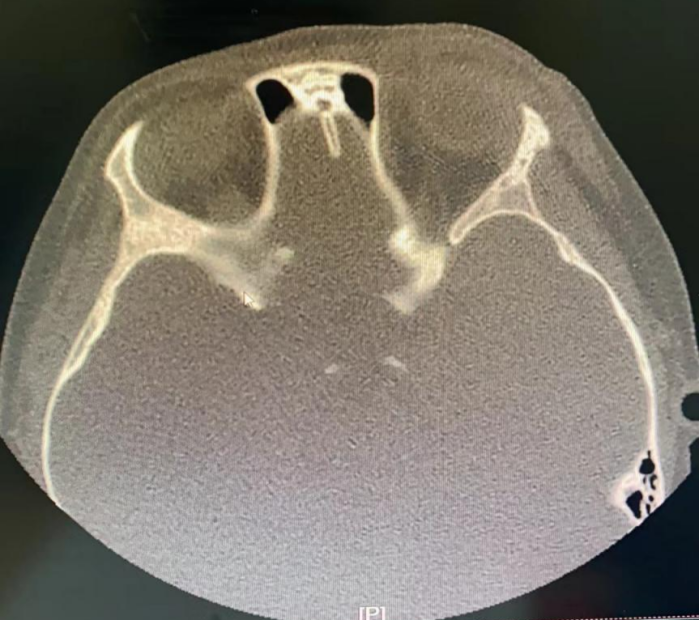

術(shù)后復(fù)查眼眶CT,異物被取出